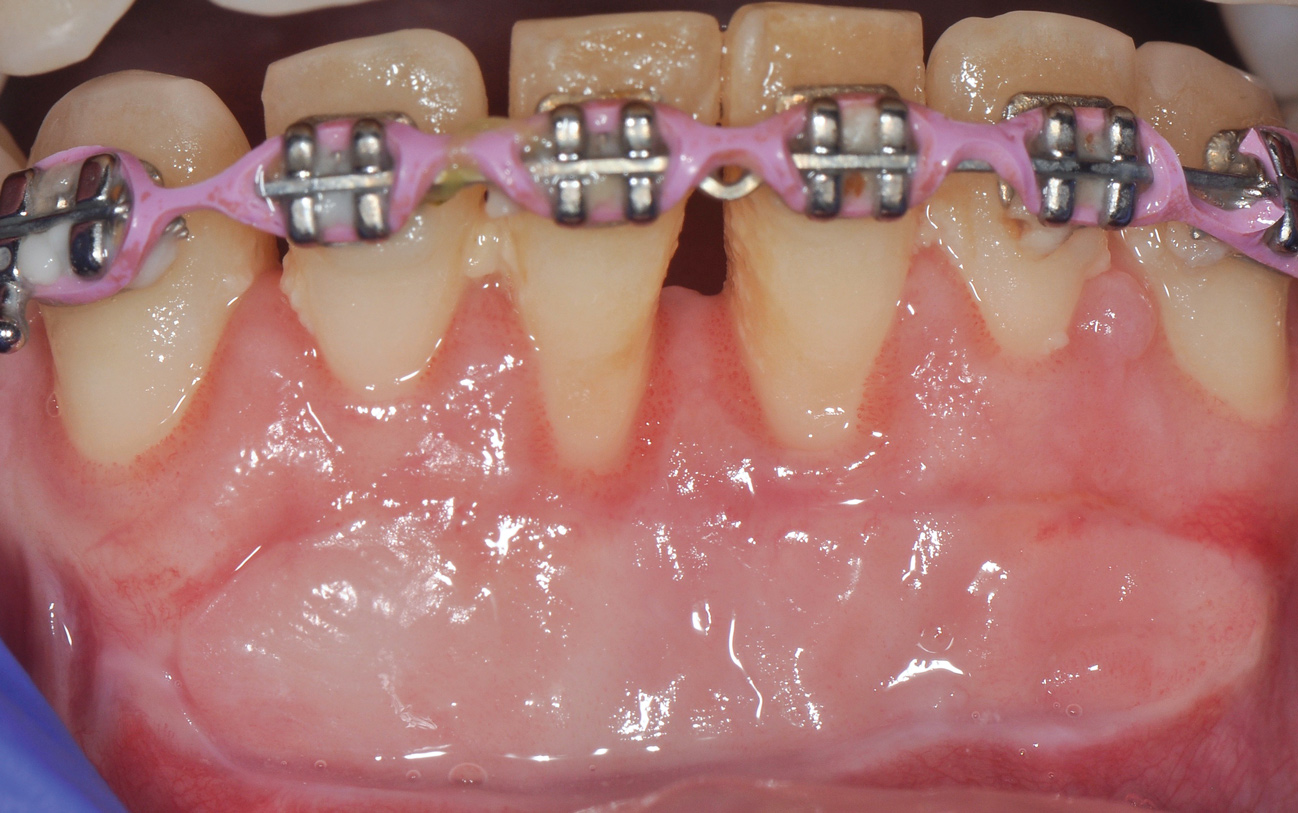

Although similar to the root coverage procedures mentioned above, gingival augmentation procedures not aimed at achieving root coverage are performed to facilitate plaque control, improve patient comfort, and prevent future periodontal recession. They may be used in conjunction with restorative, orthodontic, or prosthetic dentistry. The consensus report from the AAP's workshop group on soft-tissue non-root coverage procedures concluded that a specific minimum amount of keratinized tissue is not needed to prevent attachment loss when optimal plaque control is present; however, if plaque control is suboptimal, a minimum of 2 mm of keratinized tissue is needed. 12 A standard procedure that is recognized to predictably gain keratinized tissue is the use of an autogenous gingival graft.12 Figure 5 through Figure 8 demonstrate the healing progression of a patient with poor oral hygiene whose mucogingival defect was treated with a free gingival graft and L-PRF from the patient's own blood.

(5.) Pretreatment photo of patient with recession to be treated with a free gingival graft (harvested from the palate) and L-PRF.

Figure 5

(6.) Postoperative view of the graft donor site after 3 weeks.

Figure 6

(7.) Postoperative view of the graft recipient site after 3 weeks showing healing progress with poor oral hygiene.

Figure 7

(8.) Postoperative view of the graft recipient site after 6 months showing healing progress with poor oral hygiene.

Figure 8